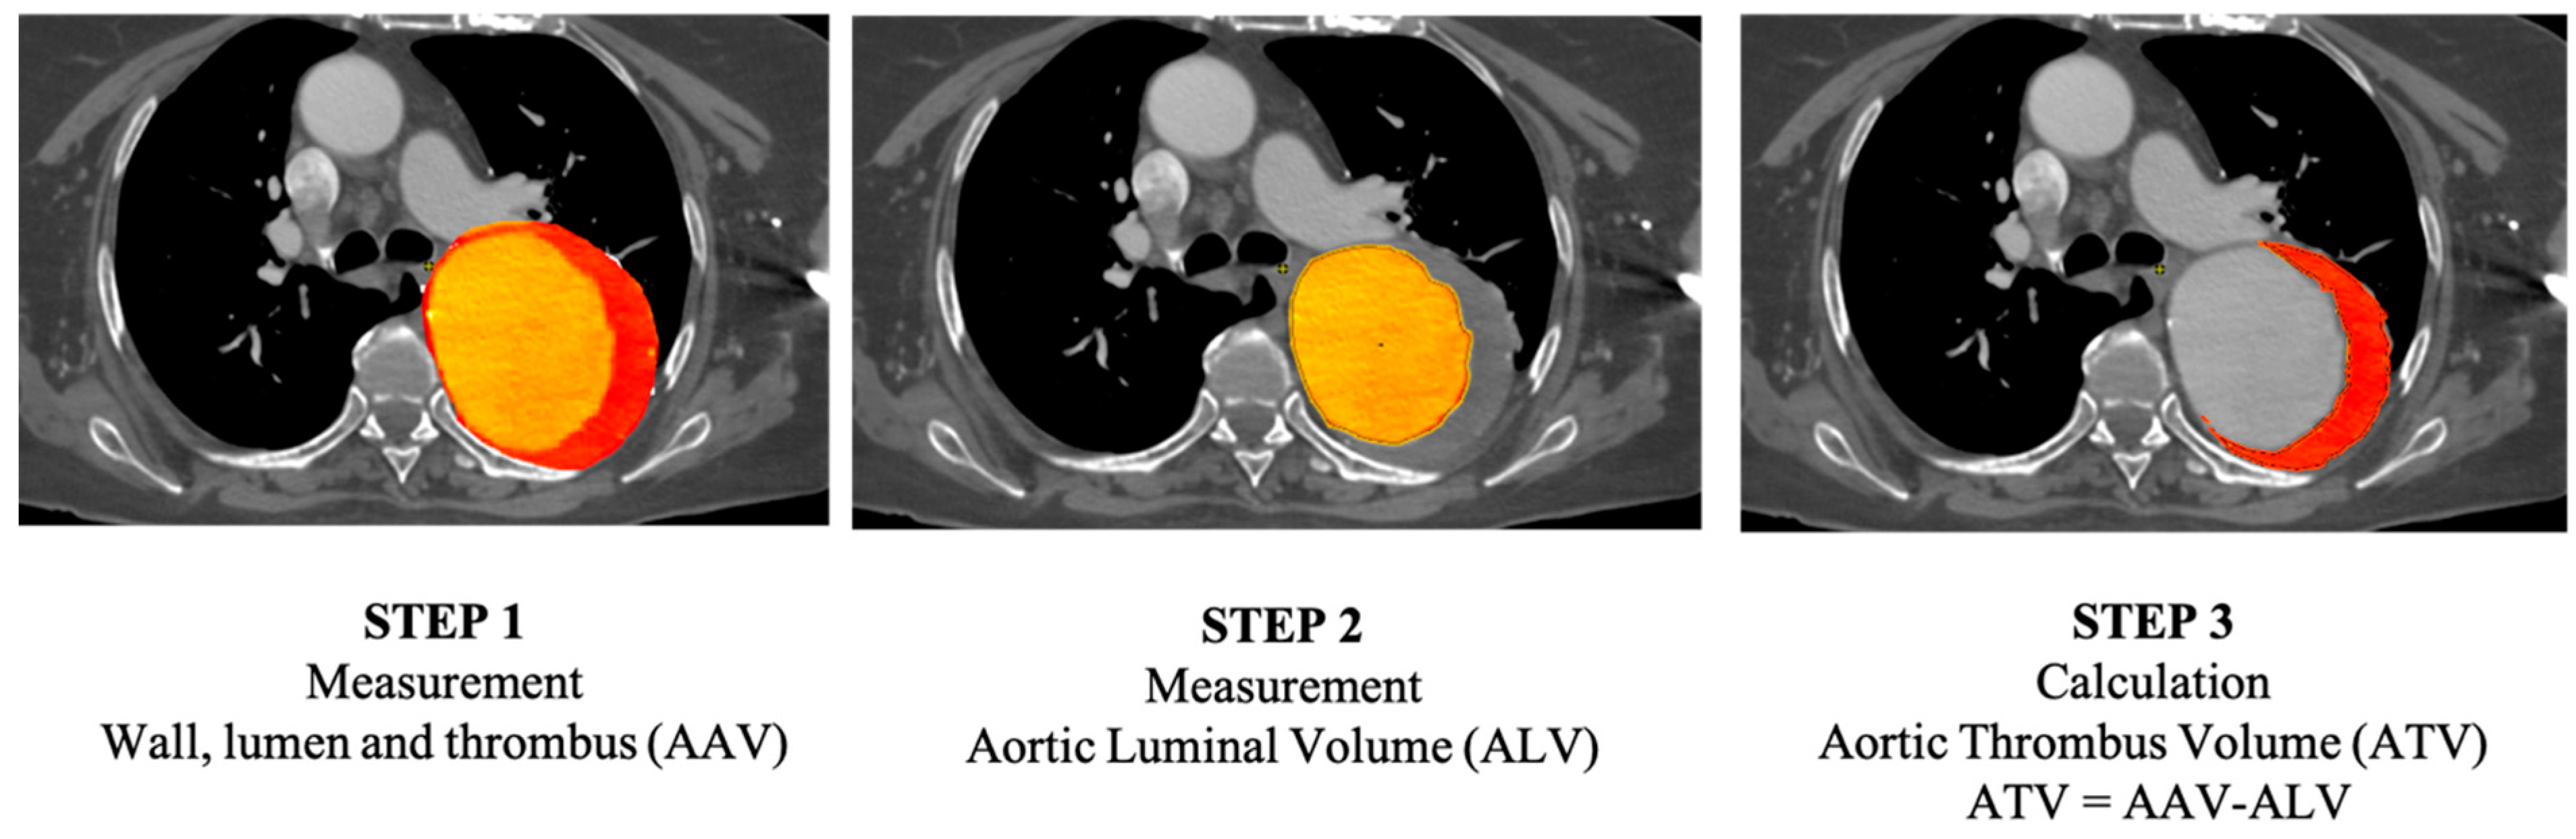

2.3. Image Analysis and Measurement Volume